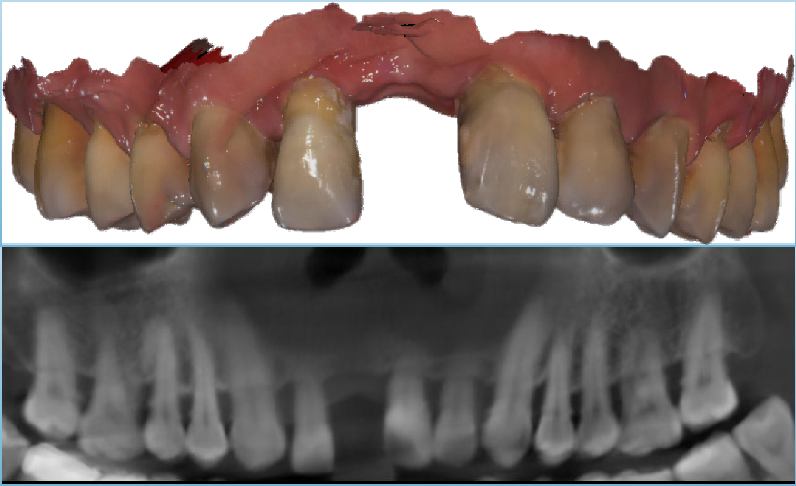

真实案例

TRUE CASE